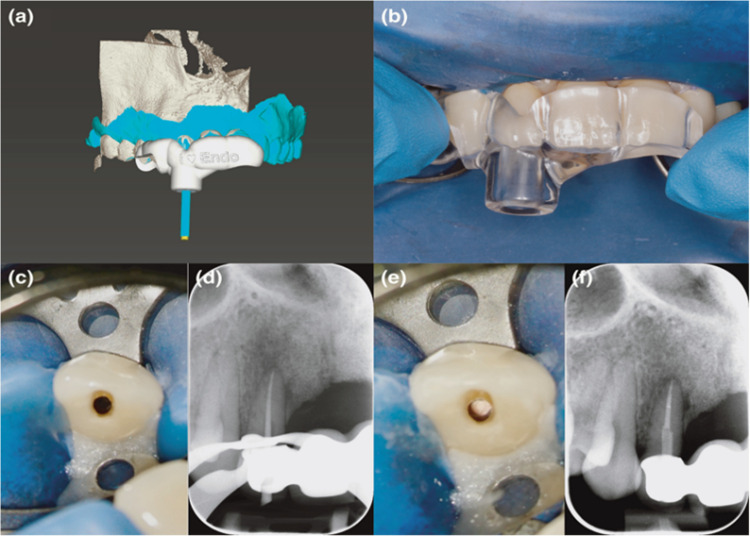

Endodontic therapy in complex clinical cases poses significant challenges, often requiring tailored approaches to achieve successful outcomes. Herein, we offer an update on the present application of GE in endodontics, which reflects good therapeutic results but also reveals limitations of the required specialized training and expertise, as well as highly costly equipment and software, which prevents its widespread adoption. This review could further contribute to research aims to advance technology to address the limitations and optimize the use of this technique in routine endodontic practice. A thorough electronic search was performed across three major scientific databases-PubMed, Web of Science, and SCOPUS-to retrieve scientific literature focusing on Guided Endodontics, encompassing both Static and Dynamic Guided Endodontics, with publications considered up to April 2025. Guided endodontics (GE), which includes SGE (static guided endodontics) and DGE (dynamic guided endodontics), is an emerging technique in dentistry that utilizes advanced imaging technology and computer-guided systems to enhance the accuracy and precision of root canal treatments, which shows great potential in the application of personalized mini-invasive treatment in complicated clinical cases with the assistant of advanced imaging technology and computer-guided systems. It also provides patients with a comfortable experience and promotes faster healing. Generally, GE is an accurate new technique that facilitates the establishment of pulp access, unblocking of calcified root canals, and mini-invasive surgical trauma in endodontic surgery, for preserving more tooth tissue while extending the preservation time of the treated tooth. Static guides and dynamic navigation have different benefits and drawbacks and should be used in specific clinical conditions.